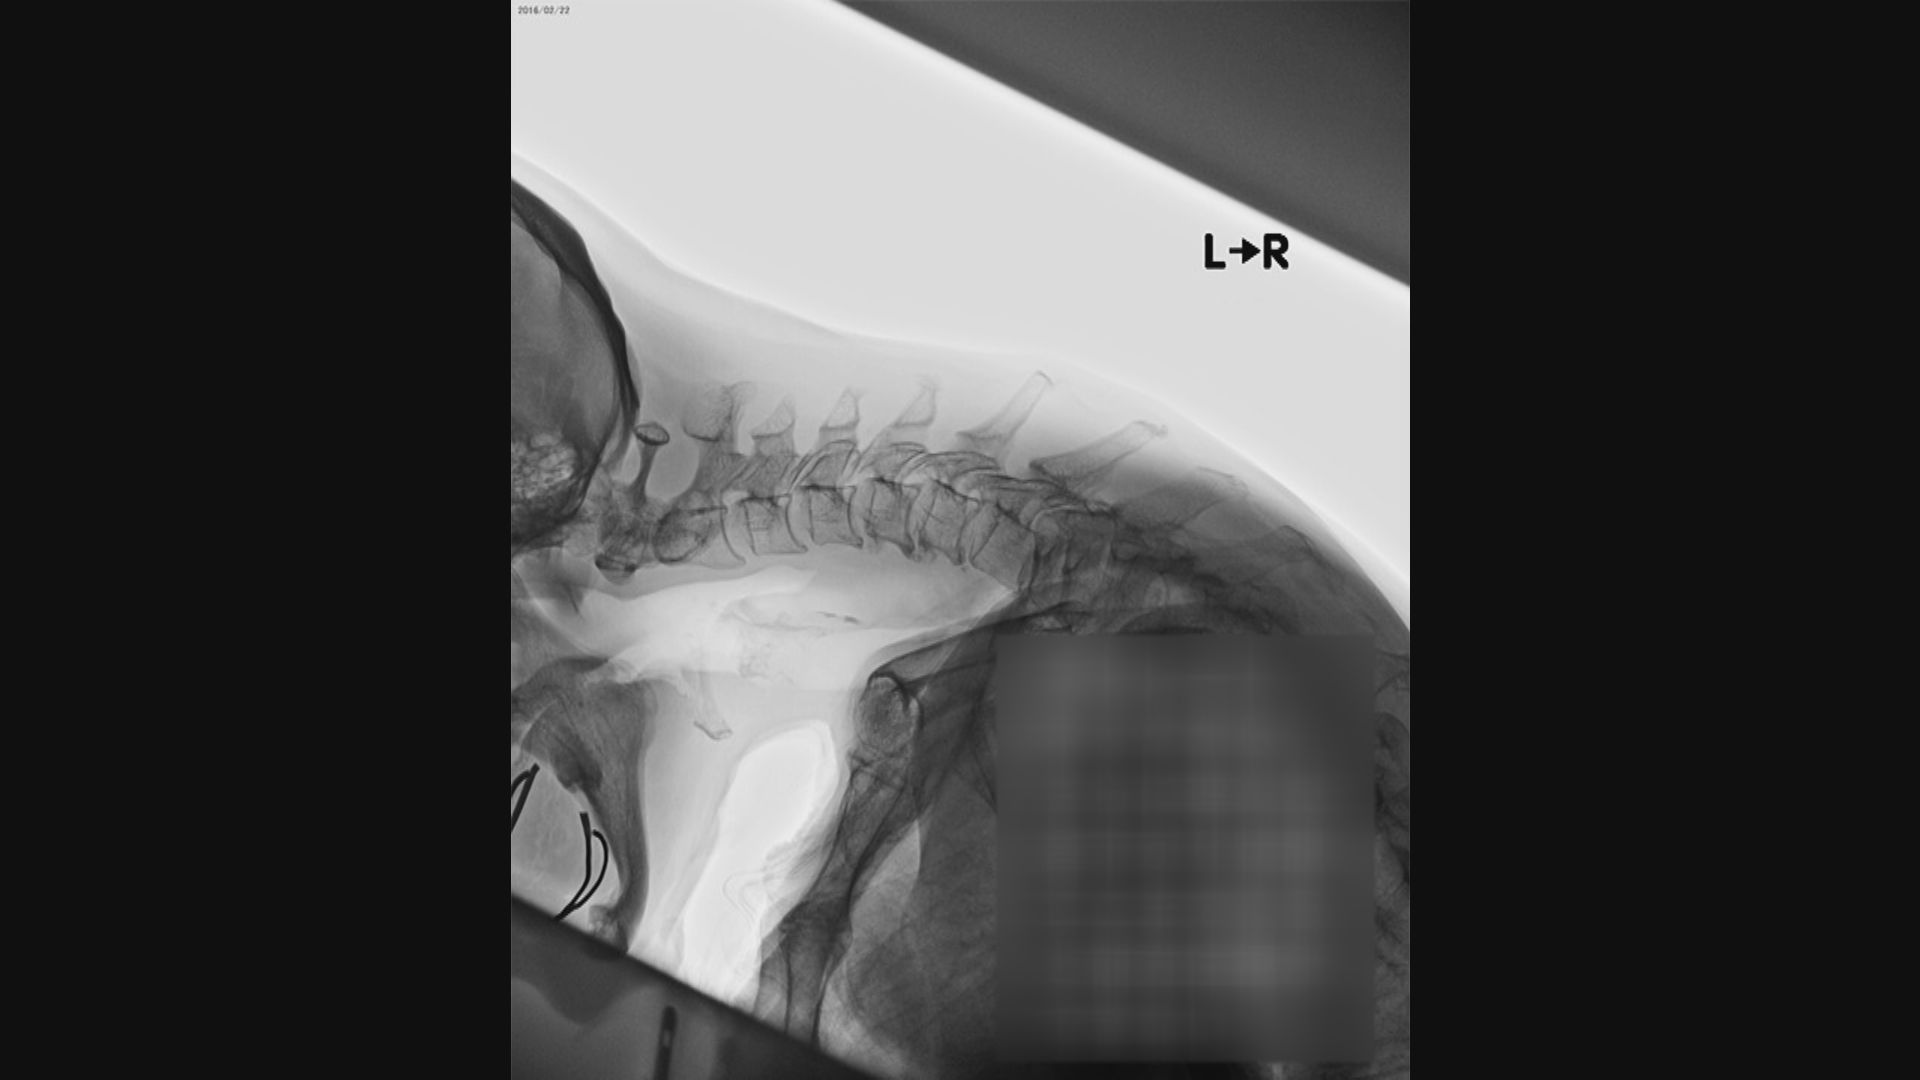

重症患者のレントゲン写真

重症患者のレントゲン写真。

かなり首が前方に倒れてしまっています。

長野赤十字病院・出口正男 整形外科部長:

「脊髄の神経が圧迫され、手足がしびれたり、動かしにくくなったりということが起こりうる」